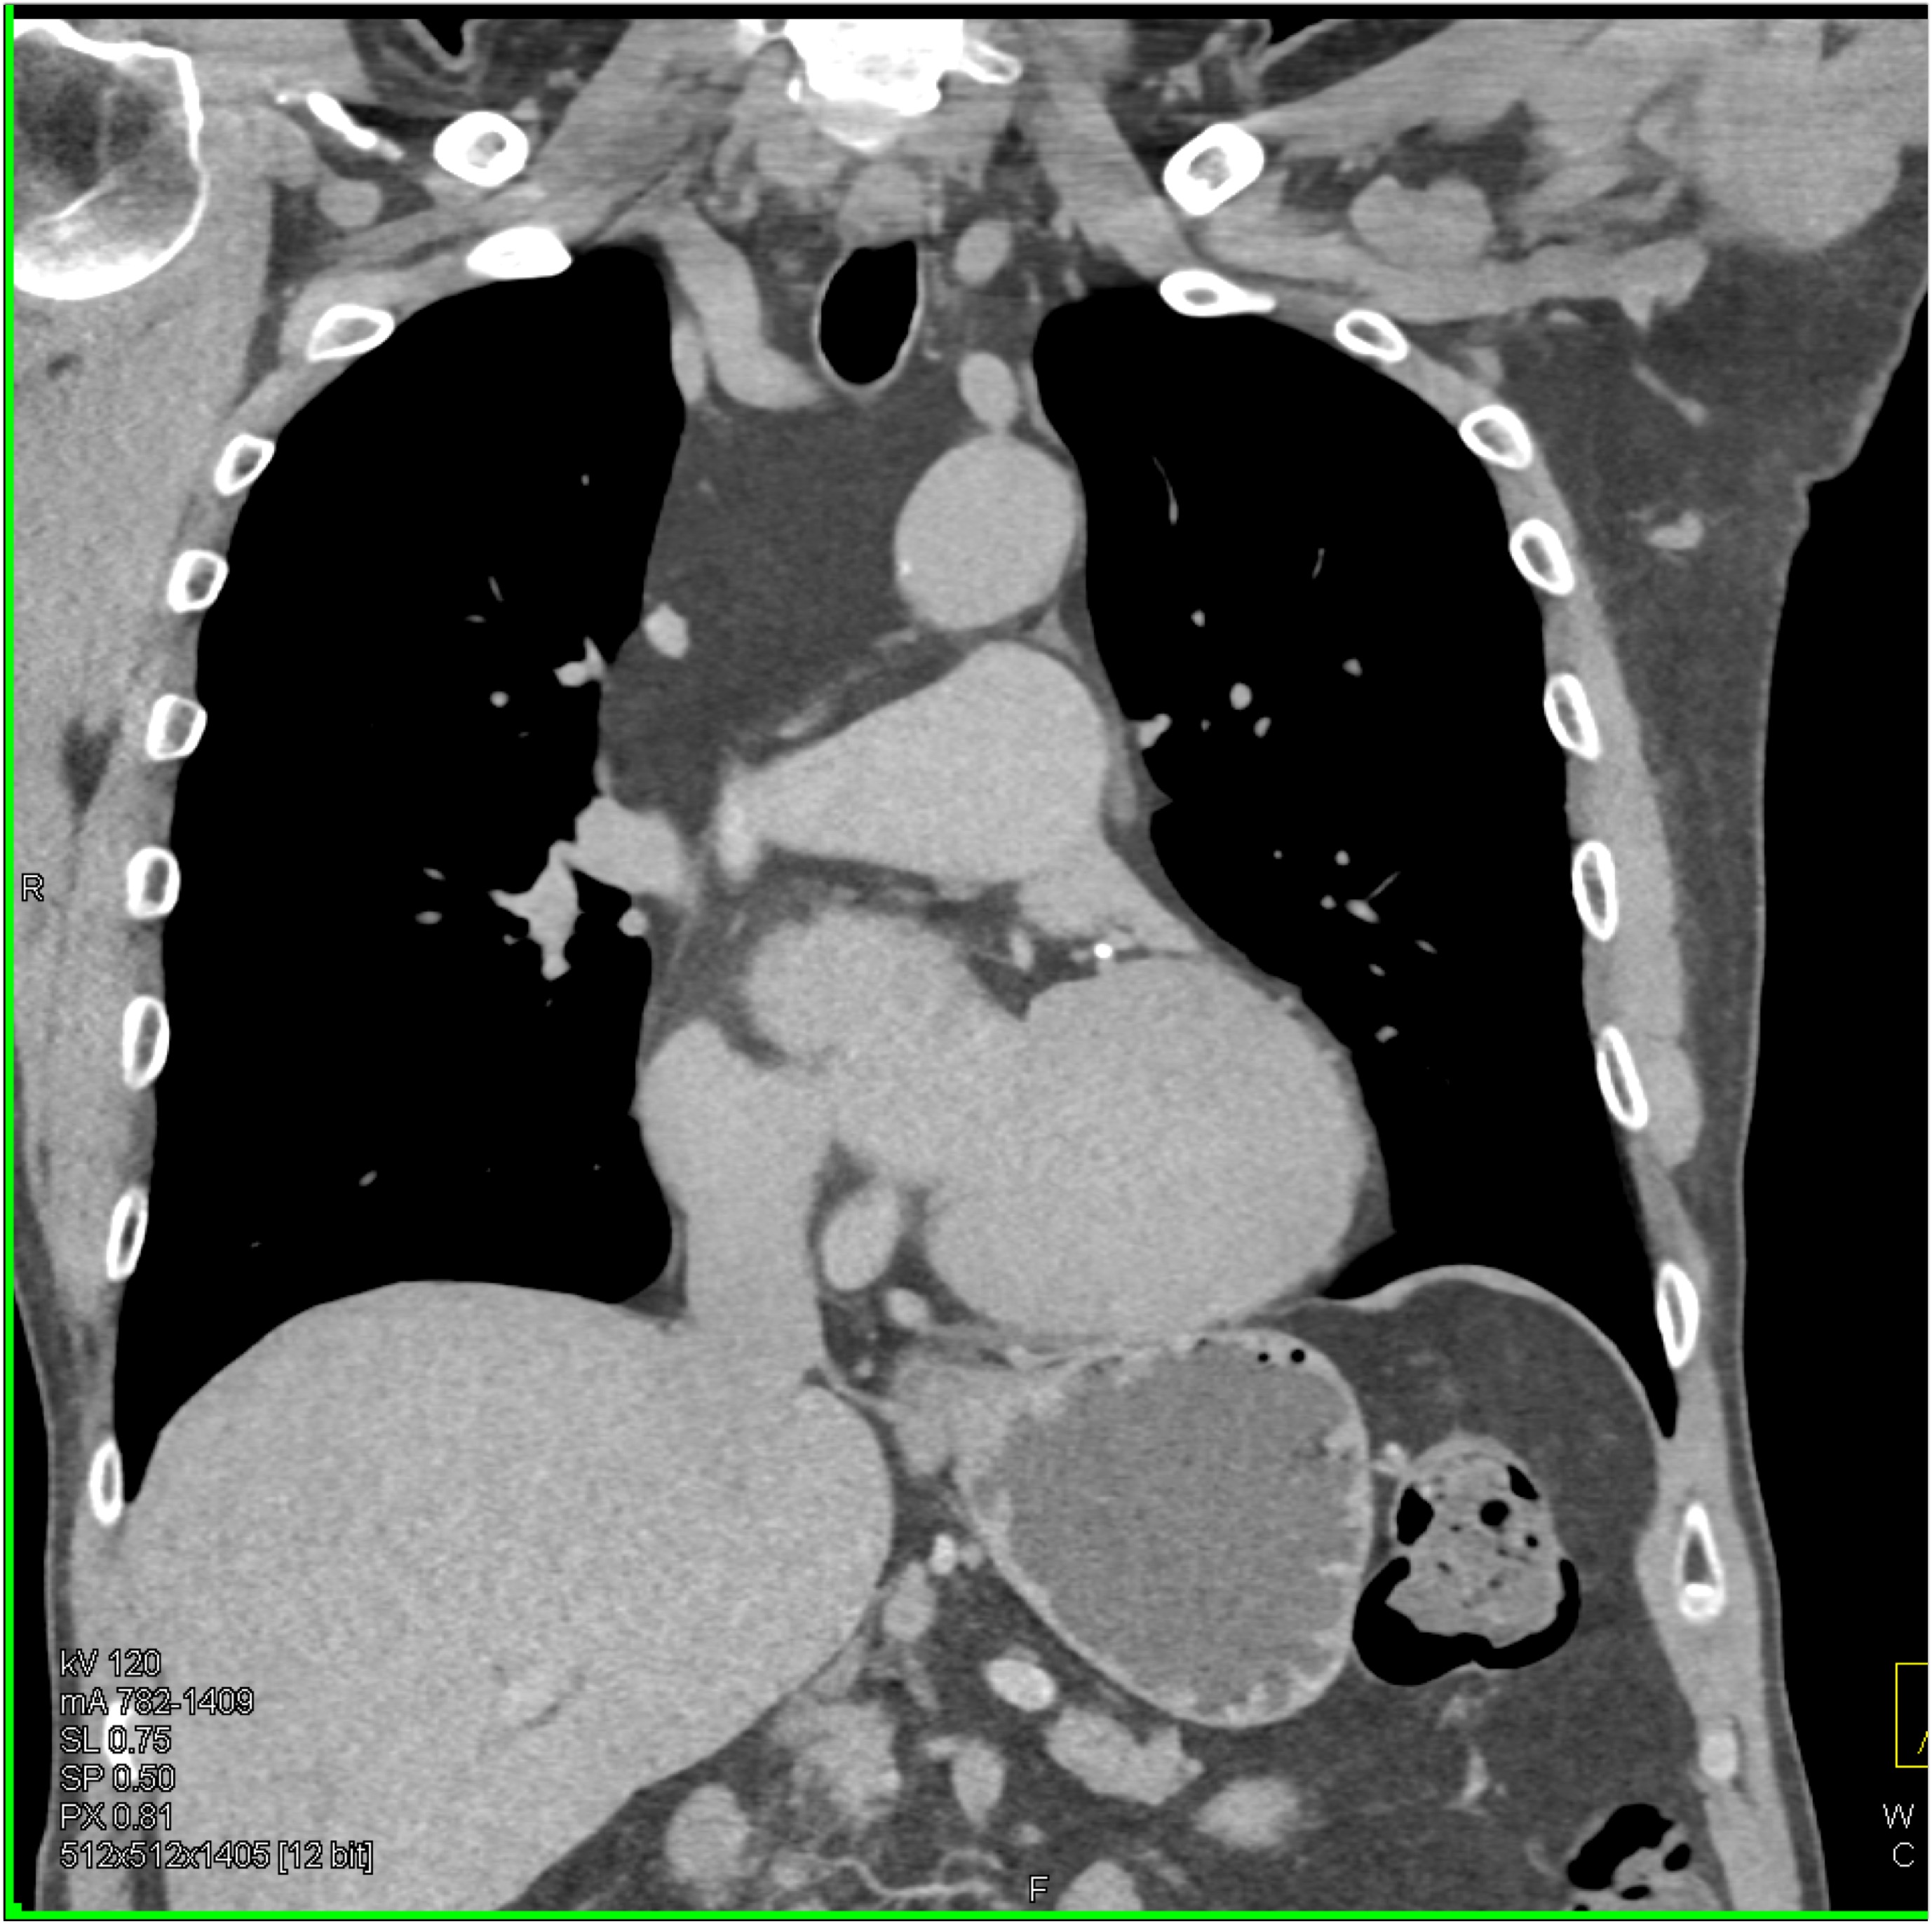

7) In this patient with mediastinal widening on CXR the best diagnosis is?

lymphoma

mediastinal lipoma

bronchogenic cyst

duplication cyst